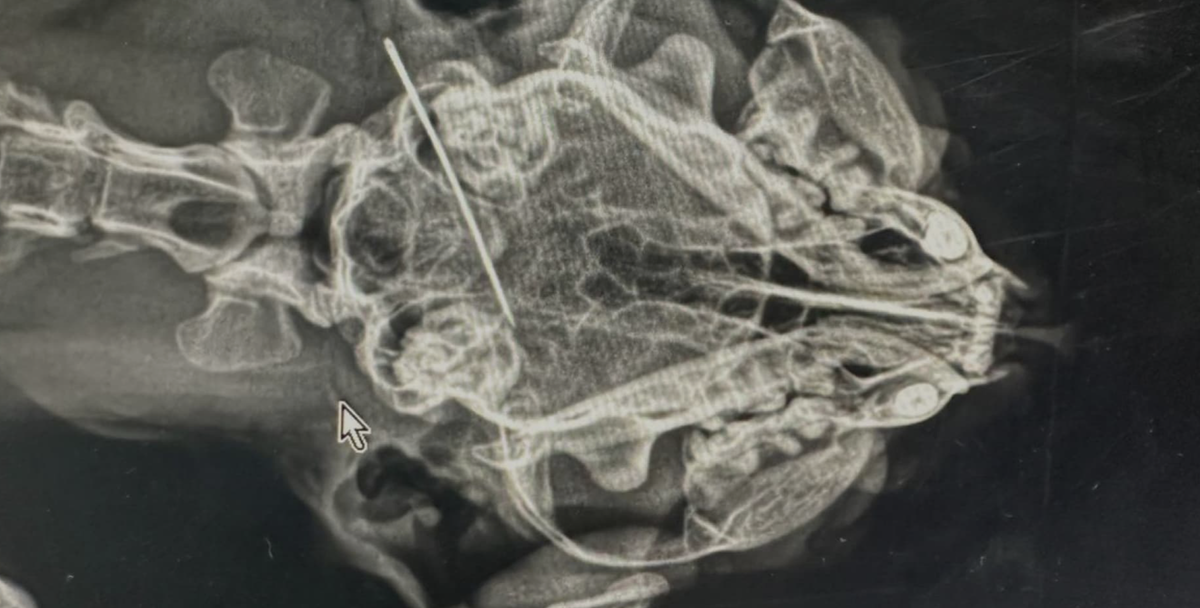

• Нитки и иголки, вся швейная история. Это очень опасно: нити могут порезать кишечник, а иголки — проткнуть стенки органов.

ЧТО ВКЛЮЧАЕТ ДИАГНОСТИКА

• Рентген-исследование.

• УЗИ брюшной полости.

• Эндоскопия (если предмет в желудке).

Если инородное тело (например, сережка или невидимка) находится в кишечнике, может потребоваться полостная операция (лапаротомия). Чтобы избежать подобных случаев, пересмотрите игрушки вашего питомца и уберите опасные предметы из зоны доступа.